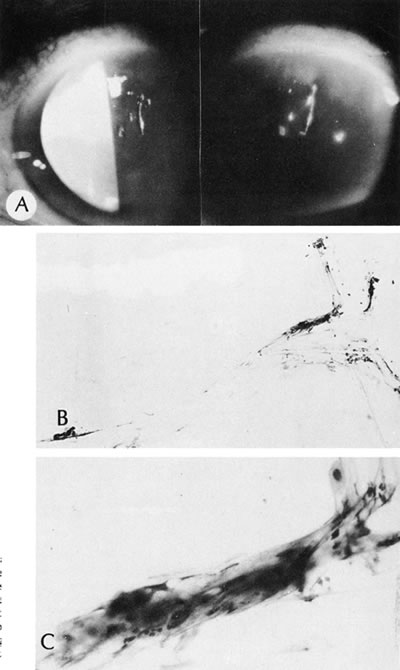

104. Waring GO3rd , Font R, Rodrigues MM et al: Alterations of Descemet's

membrane in interstitial keratitis. Am J Ophthalmol. 81:773, 1976.

105. Scattergood K, Breen E, Hirst L: Scrolls of Descemet's membrane in

healed syphilitic interstitial keratitis. Ophthalmology 90:1518, 1983.